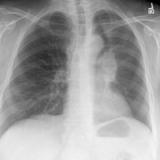

LUL collapse Case10

Date: 01/13/2008

Views: 4689